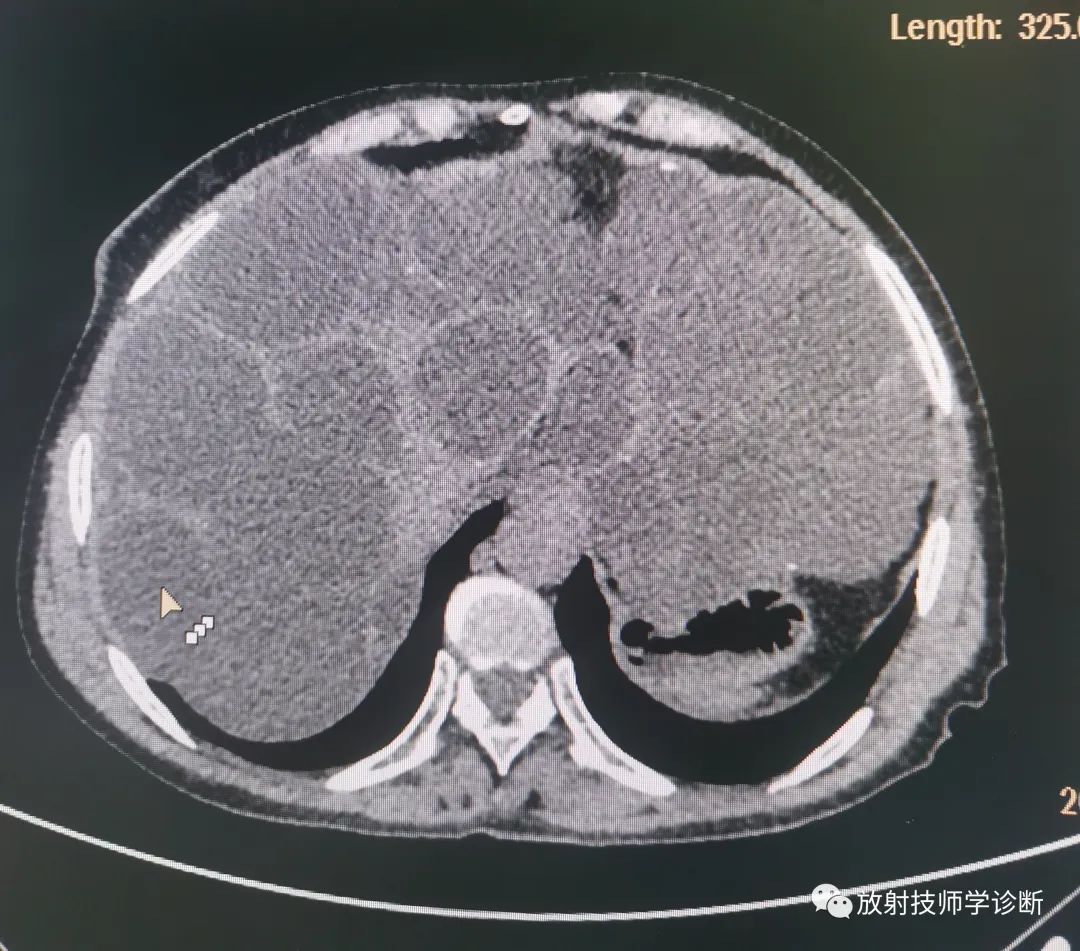

典型多囊肝

多囊肝,是一种常染色体显性遗传病,表现为肝脏的多发性弥漫损害,囊肿间的肝细胞正常,多合并多囊肾,同时在胰腺、脾脏、双肺及女性卵巢可发现囊性病变。多囊肝合并多囊肾致病基因位于人第16对常染色体上,DNA分析可作为疾病无症状时和产前的早期诊断。

(2)CT检查:可明确囊肿的大小、数目、解剖位置,并可发现1~2cm肝囊肿。CT平扫表现为肝内弥漫大小不一的水样低密度影,边缘光滑清楚,CT增强后无强化。

图片